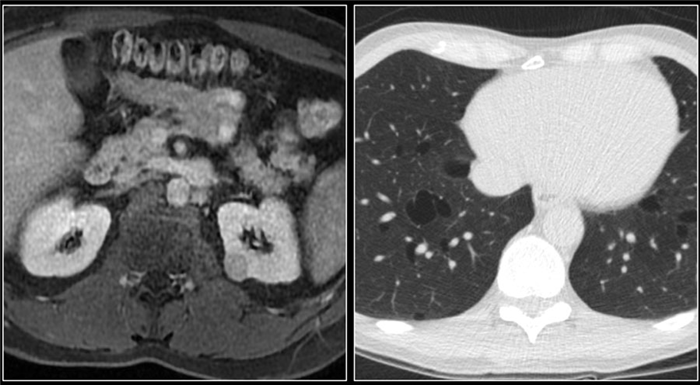

(Справа) КТ с контрастированием, аксиальная проекция: у мужчины 47 лет с остро возникшей болью в правом боку после мотоциклетной аварии выявлен травматический инфаркт правой почки вследствие тупой травмы. (Слева) КТ с контрастированием, аксиальная проекция: у мужчины 38 лет, получившего тупую травму из-за автокатастрофы, выявлен обширный инфаркт почки с отсутствием контрастирования. Обратите внимание на слабое контрастирование кортикального ободка.

(Справа) КТ с контрастированием, аксиальная проекция: у этого же пациента обнаружена только небольшая контрастируемая область левой почки. Выявлен тромбоз левой почечной артерии в результате травматического расслоения.